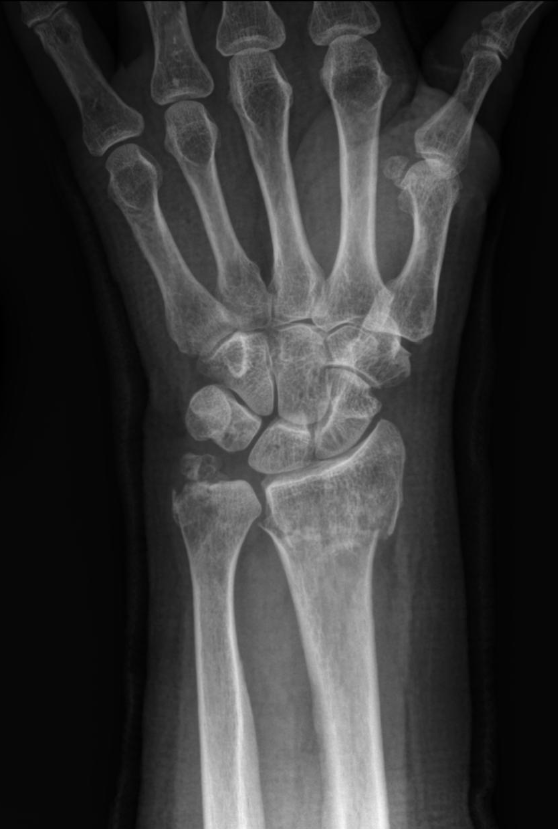

Colles' Fracture

This type of fracture is often described as being an extra-articular transverse fracture of the distal radius with dorsal displacement with/without ulnar styloid fracture. The fracture is usually around 2cm proximal to the radiocarpal joint.

1. X-Ray: AP and Later x-rays of the wrist. Oblique views of the wrist may also be beneficial. The radiological features include:

1. Dorsal tilt of the distal fragment

2. Dorsal displacement of the distal fragment

3. Ulnar styloid fracture

4. Radial shortening

5. Radial tilt

6. Radial displacement